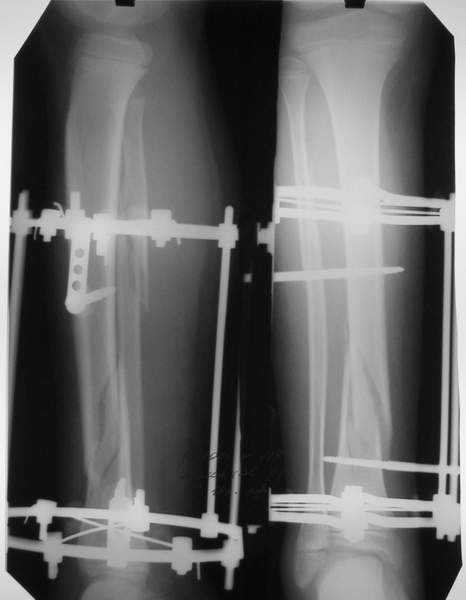

В аттачтах №№ 1 и 2 - примеры, когда 2 кольца не позволили послеоперационно

исправить смещение фрагментов большеберцовой (по ширине и вальгусное).

А казалось бы (#2) - поиграй на штангах и все влетит.

1

1a